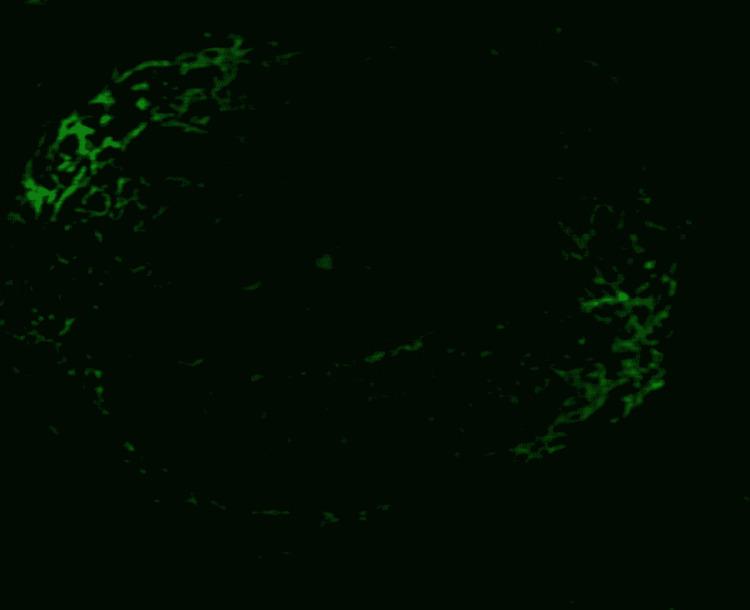

Anti-glomerular basement membrane (anti-GBM) disease is an autoimmune disorder characterized by the production of circulating immunoglobulin G (IgG) antibodies that affect the kidneys and lungs, mainly in the form of rapidly progressive crescentic glomerulonephritis and pulmonary hemorrhage. Typically diagnosed on tissue biopsy, findings mainly include glomerular crescent formation, bright linear staining of GBM for IgG on direct immunofluorescence (IF), and the serologic presence of circulating anti-GBM antibodies. Variation in the laboratory results, where histological findings of linear IgG IF staining were present in the absence of circulating anti-GBM antibodies, have recently led to the use of the term "atypical anti-GBM disease," which usually has a distinct benign clinical outcome as compared to typical anti-GBM disease. We report a case of a middle-aged woman who presented with renal failure without lung involvement. Upon further investigation, the patient was found to have strongly positive serum anti-GBM antibodies, but the tissue biopsy did not show typical findings of the anti-GBM disease. The patient showed modest improvement after multiple sessions of plasmapheresis and steroids, with stabilization of her renal parameters after the initial response. In our case, we will address the possibilities of the discrepancies between the serological and histopathological findings.

抗肾小球基底膜(anti-GBM)病是一种自身免疫性疾病,其特征是产生循环免疫球蛋白G(IgG)抗体,主要以快速进展性新月体性肾小球肾炎和肺出血的形式影响肾脏和肺。通常通过组织活检进行诊断,主要发现包括肾小球新月体形成、直接免疫荧光(IF)下GBM对IgG的明亮线性染色以及循环抗GBM抗体的血清学存在。实验室结果存在差异,即在线性IgG IF染色的组织学发现存在时却没有循环抗GBM抗体,这最近导致了“非典型抗GBM病”这一术语的使用,与典型抗GBM病相比,其通常具有明显不同的良性临床结局。我们报告一例中年女性病例,该患者出现肾衰竭但无肺部受累。进一步检查发现,患者血清抗GBM抗体呈强阳性,但组织活检未显示抗GBM病的典型表现。经过多次血浆置换和类固醇治疗后,患者病情有适度改善,初始反应后肾脏参数稳定。在我们的病例中,我们将探讨血清学和组织病理学结果之间差异的可能性。